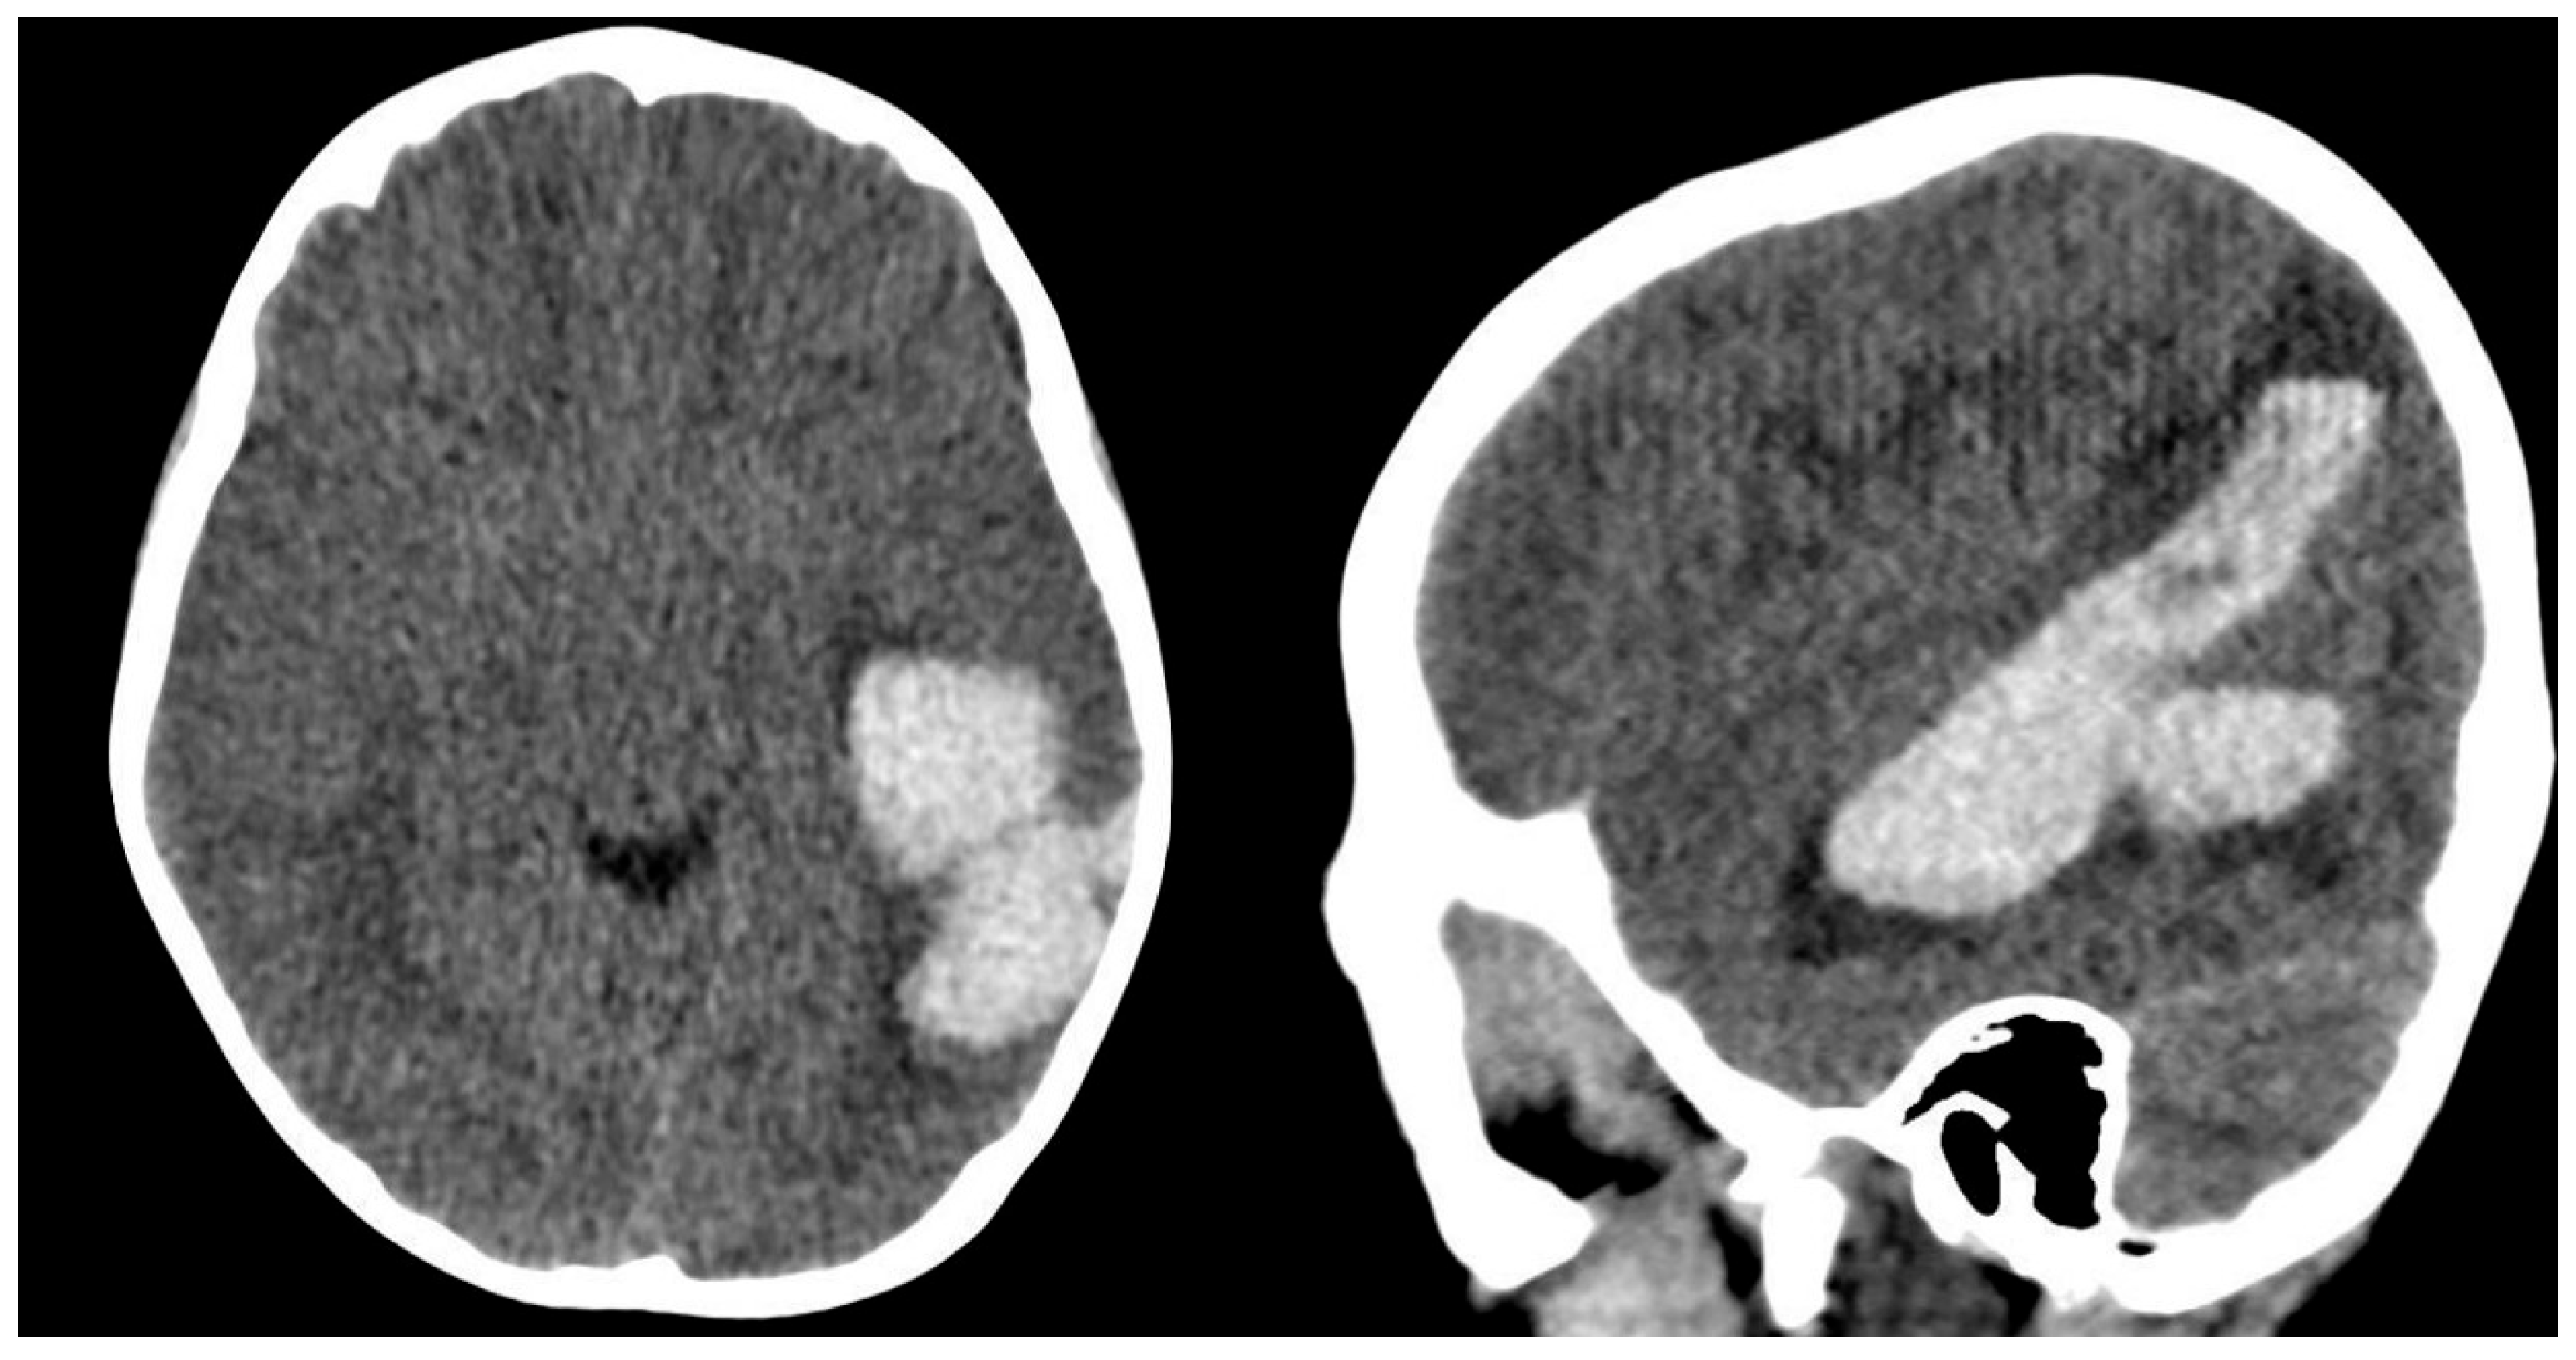

A 6-year-old boy presented to the emergency department two years ago with sudden onset of headache accompanied by nausea and vomiting. Neurological examination was unremarkable, revealing no pathological findings. A brain CT scan demonstrated an intracerebral hematoma located in the left posterior temporal region (Figure 1).

Figure 1. CT imaging of the brain at the time of the initial evaluation two years earlier.